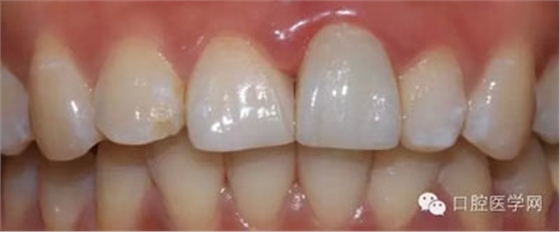

1、術(shù)前比色照

將比色照飽和度調(diào)到最低有助于牙齒明度的選擇

將比色照的飽和度調(diào)到最高有助于牙齒道飽和度選擇